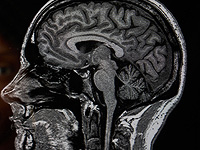

Первые тревожные изменения в поведении сына Фэрбэрн заметила вскоре после своей свадьбы с отчимом Андре, Аластером, в ноябре 2022 года. Молодой человек стал более рассеянным и иногда вел себя неадекватно. Обследование в университетской больнице Норфолка и Норвича выявило необычное уменьшение объема мозга, а окончательный диагноз был поставлен в больнице Адденбрука в Кембридже.